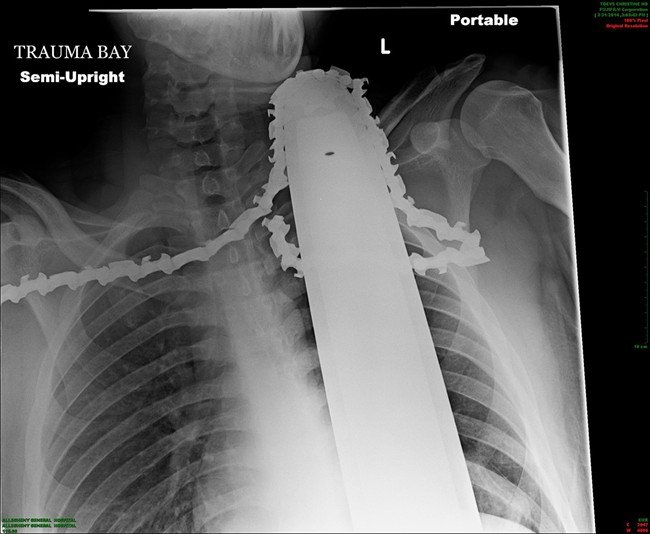

Οπως φαίνεται και από τος ακτινογραφίες, το αλυσοπρίονο διακρίνεται καθαρά στο λαιμό του 21χρονου άντρα.

Ο James Valentine είχε σκαρφαλώσει σε ένα δέντρο, στην περιοχή Ross, όταν είδε τη ζωή του να κινδυνεύει σοβαρά από ένα απίθανο ατύχημα. Λόγω ατυχών χειρισμών, το αλυσοπρίονο που χειριζόταν, έπεσε και σφηνώθηκε στο λαιμό του. Συνάδελφός του και αυτόπτης μάρτυρας, τον βοήθησε να κατέβει από το δέντρο και τον μετέφερε στο πλησιέστερο νοσοκομείο.